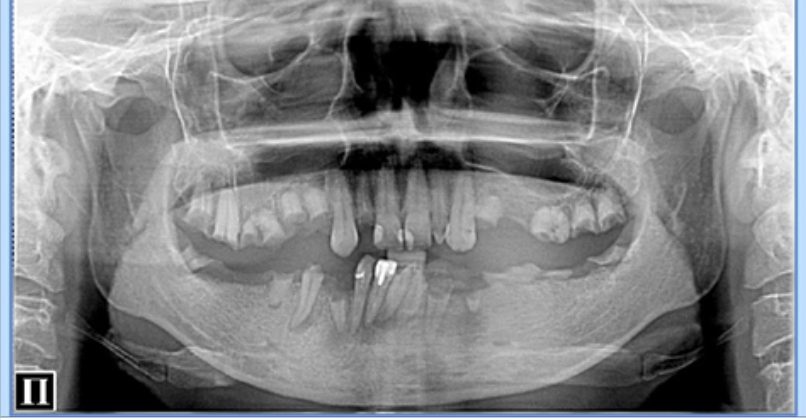

Обратилась к нам с жалобами на неприятный запах изо рта, желанием сделать профессиональную чистку зубок и составить план лечения. После проведенной процедуры было предложено сделать обзорный снимок и опираясь на него составить план работ. Услышав то, что у нее есть что-то кроме «малюсенького кариеса где-то внизу» и что план работ включает в себя серьезное лечение зубов (перелечивание каналов, замену «мостов» и протезирование в перспективе), были сделаны большие и круглые глаза и сказано, что я м#д@к и разводила а у нее все отлично и вообще ей в поликлинике сказали, что зубы идеальные. В общем, я остался крайним и получил персональную жалобу на «сайте для ябед».